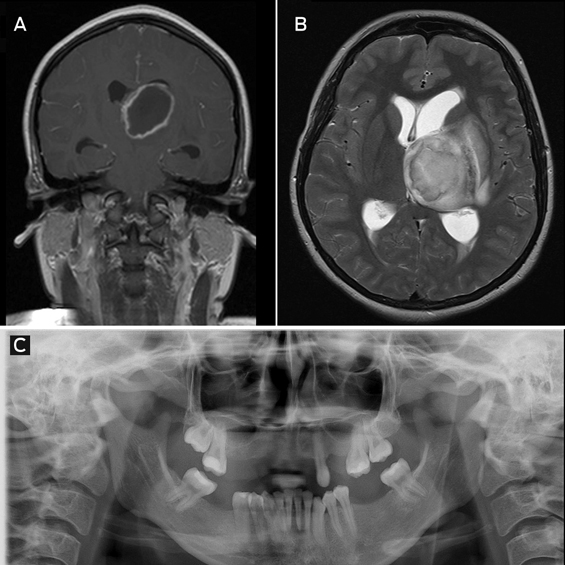

Magnetic resonance imaging showed a 4.6 × 5.1 cm ring-enhancing lesion in the left thalamus, with extensive surrounding oedema (Figure, A and B).

Microscopy of a biopsy sample showed pus and gram-positive cocci. Cultures grew Streptococcus anginosus (also known as Streptococcus milleri), an organism that is part of normal oral flora and a well known cause of metastatic abscesses.

The patient admitted to undergoing multiple recent tooth extractions (Figure, C). She was treated with 6 weeks of intravenous benzylpenicillin and made a full recovery, with complete abscess resolution on follow-up imaging.